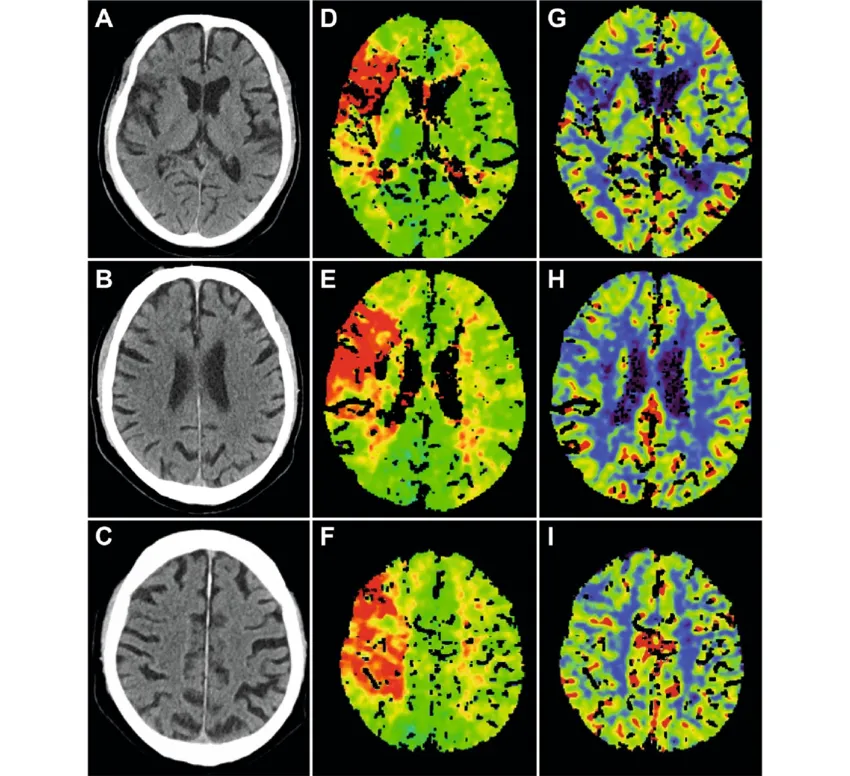

5. IVIM Simplified: Non-Contrast Perfusion Imaging with Dr. Zainab Vora

IVIM is the future of non-contrast MRI, and this lecture makes it accessible.

• The concept of Intravoxel Incoherent Motion

• How D, D*, and F parameters work

• When IVIM trumps conventional DWI

• Clinical utility in tumours, fibrosis, and stroke